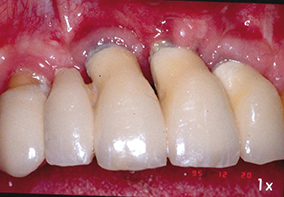

7 - Démonstration et conseils d’hygiène pour assurer la maintenance post-prothétique (praticien maître d’œuvre de la prothèse).

8 - Échec dû à une mauvaise interprétation des études pré-implantaires et une certaine négligence au niveau de l’hygiène.